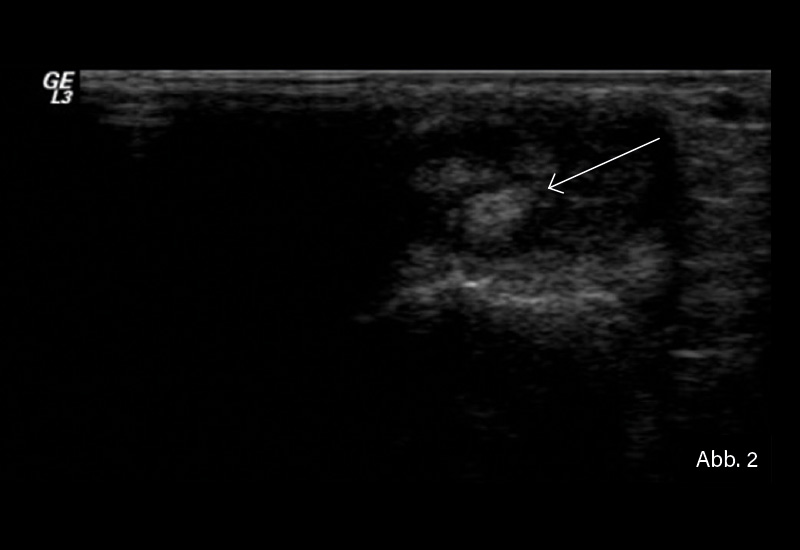

BILDGEBENDE DIAGNOSTIK: Gelenksonografie

DIAGNOSE: Tenosynovitis der Sehne des Musculus extensor carpi ulnaris

bei seropositiver RA

Der sonografische Nachweis einer Tenosynovitis der Sehne des Musculus extensor carpi ulnaris (ECU) spielt eine entscheidende Rolle in der Frühdiagnostik der RA. Die frühzeitige Erkennung entzündlicher Veränderungen ermöglicht eine zeitnahe therapeutische Intervention, die den Krankheitsverlauf positiv beeinflussen kann. Die RA manifestiert sich häufig zunächst an den Händen und Handgelenken. Dabei ist die Tenosynovitis der ECU-Sehne ein häufiger Befund. In einer Studie wurde Tenosynovitis bei mindestens einem anatomischen Ort bei 48,8 % der RA-Patienten festgestellt, wobei die ECU-Sehne zu den am häufigsten betroffenen Sehnen gehörte.